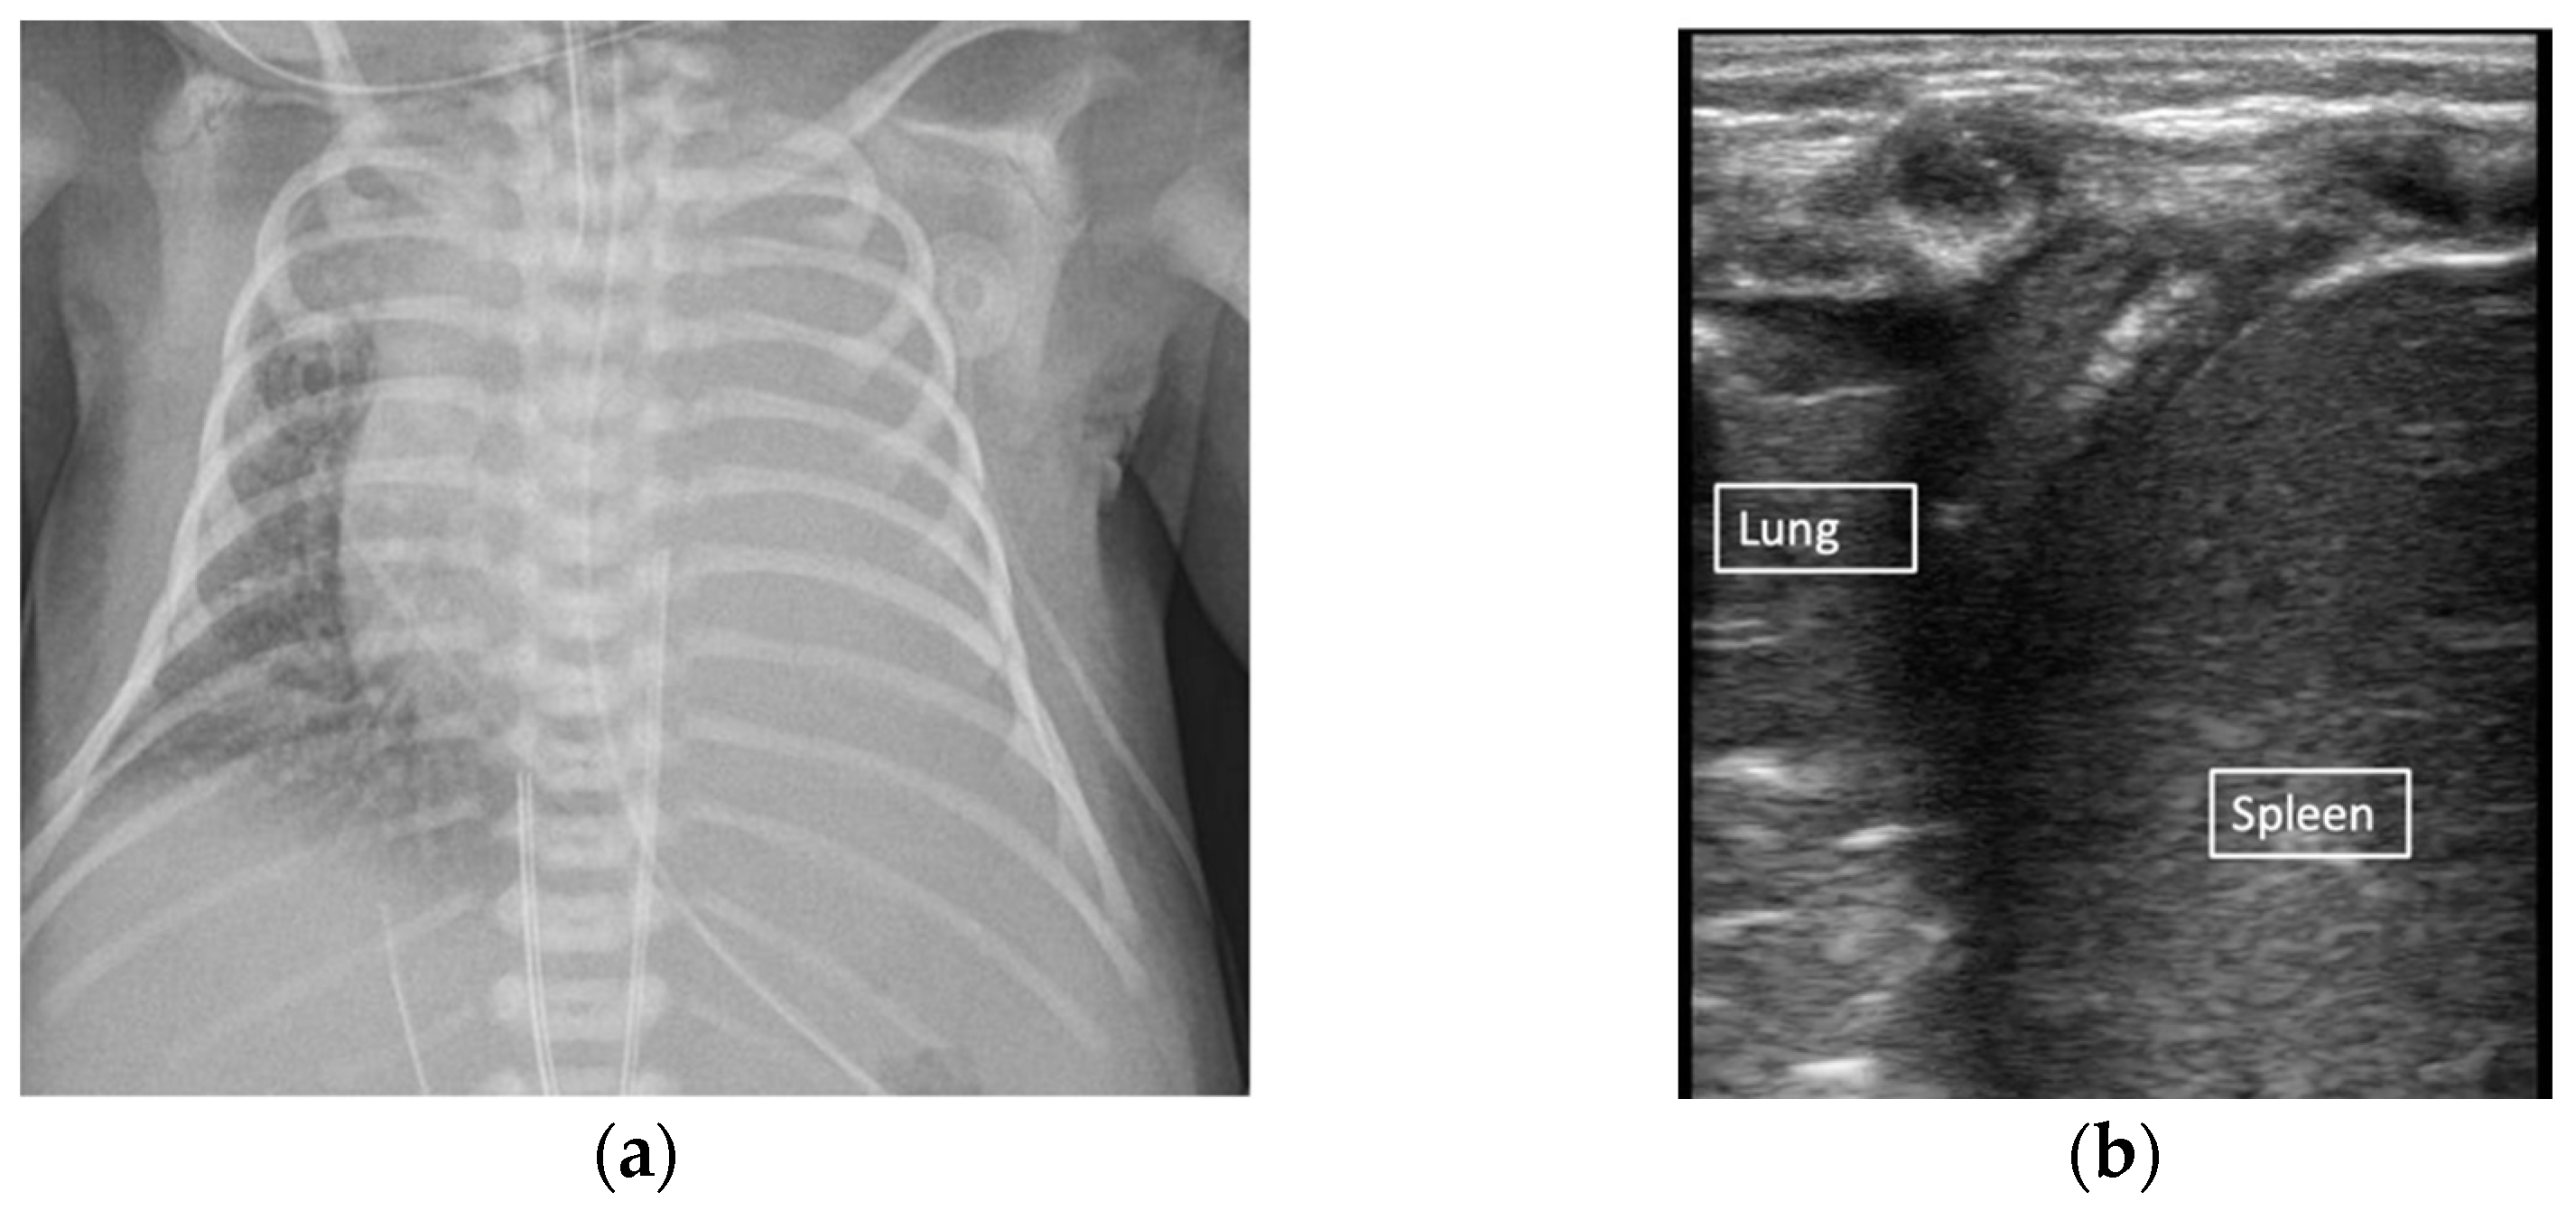

2.2. Pneumothorax

2.3. Atelectasis